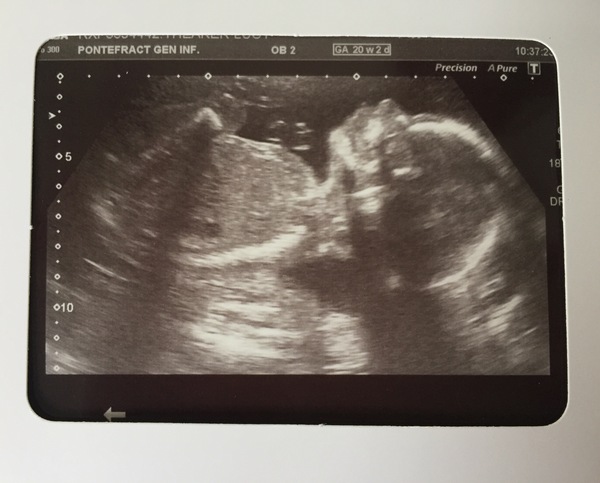

Thisisbonkers · 13/07/2016 13:54

You'll all be reassured to know that the baby is still there Grin

I have an anterior placenta which would explain lack of movement so far (feeling of, it's still wriggling around in there!). One minor note of concern is left kidney slightly more filled than the other but is (just) inside normal parameters. It's been noted but no further scan required. I hope it's nothing!

Thisisbonkers · 13/07/2016 13:56

And the obligatory photo!

Lovely photo bonkers, pleased to hear all is well and only an anterior placenta dulling the movement.

bonkers that picture is lovely. Are they going to re scan you at a later date to check the fluid levels?

Lovely photo bonkers, good to hear that they're not worried about baby's kidney. I know it's not the same, but a few months back dd2 had a kidney ultrasound and they found cysts, nothing to worry about but noted all the same.

20 weeks 2 days today. Still team yellow for me! Here is trouble! 😍

Lovely scan thisisbonkers 😍